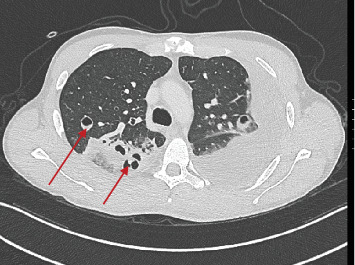

Lemierre综合征(LS)是一种罕见的疾病,估计每年发病率为1-10/1,000,000,定义为口腔和鼻咽感染伴继发性败血症导致脓毒性栓塞和颈内静脉血栓形成的并发症。1936年,在抗生素发明之前,安德烈·勒米尔首次描述了这种综合征。在抗生素出现之前的时代,这是一种常见的疾病,其特征通常是在7-15天内致命,死亡率可高达80%。随着抗生素治疗的发展,LS的发病率迅速下降,如今,它也被称为“被遗忘的疾病”,但死亡率仍然很高(5%),特别是在诊断延迟和治疗不当的情况下。我们提出了一个23岁的病例,他被转介到我们医院,因为咽炎后呼吸困难加剧并伴有高烧,以提高人们对这种严重罕见疾病的认识。如果立即开始适当的治疗,长期的结果通常是好的。肺和血管方面的主要治疗是抗生素治疗,加或不加抗凝和胸管引流。

Lemierre syndrome (LS) is a rare condition with an estimated incidence of 1-10/1,000,000 per year defined as a complication of an oral and nasopharyngeal infection with secondary septicemia leading to septic emboli and internal jugular vein thrombosis. This syndrome was first described by Andre' Lemierre in 1936, before the development of antibiotics. In the preantibiotic era, it was a common condition and it was often characterized by a fatal course within 7-15 days with a mortality rate that could reach up to 80% of cases. After the development of antibiotic therapies, the incidence of LS rapidly declined, and nowadays, it is also known as "the forgotten disease," but the mortality risk remains high (5%) especially in case of diagnostic delay and inappropriate therapies. We presented a case of a 23-year-old who was referred to our hospital for worsening dyspnea associated with high fever following a pharyngitis in order to raise awareness about this severe rare disease. Long-term outcomes are usually good if proper treatment is started with no delay. The mainstays of treatment for the pulmonary and vascular aspects are antibiotic treatment with or without anticoagulation and chest-tube drainage.